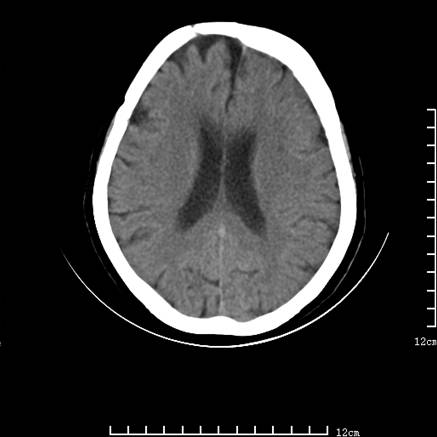

标题: V0514:女,72岁,偶有头晕,自诉记忆力减退,来诊。 [打印本页]

标题: V0514:女,72岁,偶有头晕,自诉记忆力减退,来诊。

1、考虑垂体腺瘤。

2、脑萎缩ct表现。

垂体腺瘤可能性大!另:轻度脑萎缩!

考虑垂体腺瘤可能性大。脑萎缩。

考虑垂体腺瘤可能性大。脑萎缩。  建议mri 检查

垂体瘤,建议mri

垂体腺瘤